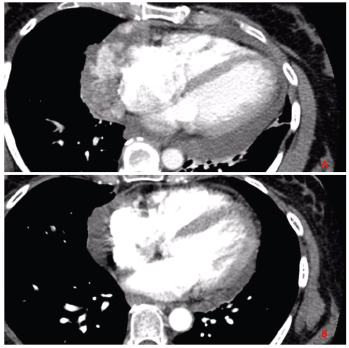

Labs at presentation were remarkable for normochromic normocytic anaemia (Hb-11.4 gm/dL) only. The comprehensive metabolic panel, troponin-I and B-natriuretic peptide were normal at presentation. The bedside echocardiogram revealed an ejection fraction of 55%–60%, normal valvular structures, and a moderate, free-flowing, concentric pericardial effusion without tamponade physiology. CT scan of the chest revealed pericardial effusion with a possible pericardial sac mass and multiple bilateral hemorrhagic pulmonary nodules. Cardiac CT showed a highly vascular, right atrial wall soft tissue mass involving the adjacent pericardium associated with large pericardial effusion (Figure 1). CT guided biopsy of the mass showed a tumour with spindle and epithelioid cells, prominent nucleoli and irregular vascular channels (Figure 2). CD31 and CD34 stains were positive in the tumour cells and highlighted the vasculature. The tumour cells were negative for keratin AE1/AE3, EMA, BerEP4, CK7, TTF-1, calretinin, CK5/6, MART-1, HMB45 and S-100.

Figure 1. Panel A: CT chest with contrast before initiating chemotherapy shows invasive mass diffusely involving the pericardium and lateral right atrial wall. Panel B: CT chest with contrast after completion of chemotherapy showing partial response in the primary tumour.

The patient had metastatic disease at the time of diagnosis. She was treated with AIM 75/10,000 regimen (doxorubicin 25 mg/m2 on day 1–3, ifosfamide 2,000 mg/m2 on day 1–5 with mesna and granulocyte colony-stimulating factor support). She completed six cycles of treatment with 25% dose reduction and minor treatment delays due to two episodes neutropenic fever. A partial response was noted after six cycles with at least 50% reduction in the tumour burden. However, within 6 weeks of completing treatment, she was diagnosed with progressive disease and opted for hospice.